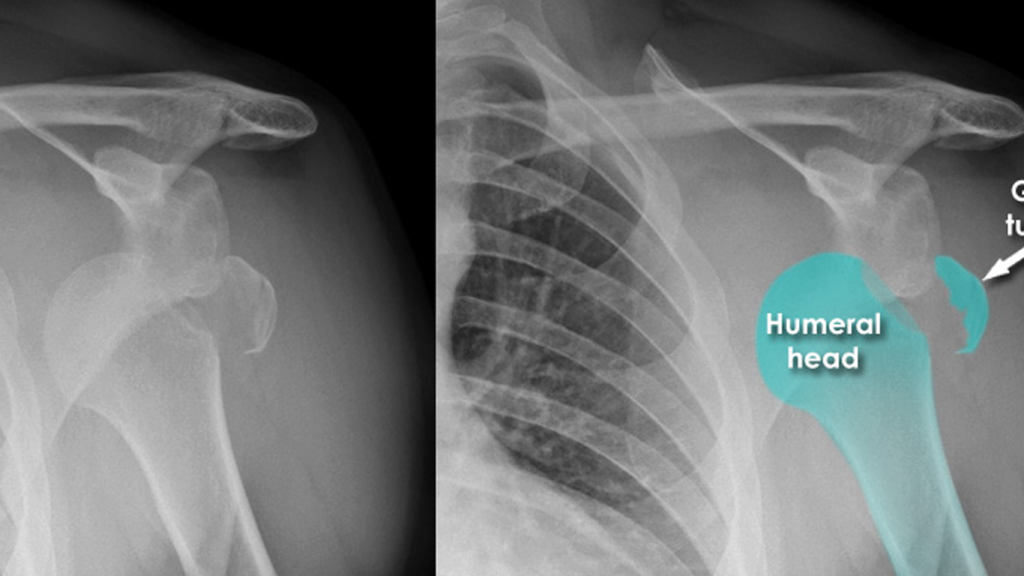

راه های تشخیص در رفتگی کتف چیست؟

تشخیص دررفتگی کتف معمولاً با بررسی علائم بالینی و انجام تصویربرداری پزشکی صورت میگیرد. پزشک ابتدا با مشاهده تغییر شکل ظاهری شانه، بررسی دامنه حرکتی، و ارزیابی درد و تورم، به احتمال دررفتگی پی میبرد. سپس برای تأیید تشخیص، از تصویربرداریهایی مانند رادیوگرافی (X-ray) استفاده میشود تا محل دقیق استخوان و نوع دررفتگی مشخص شود. در موارد پیچیدهتر یا برای بررسی آسیب به بافتهای نرم، ممکن است MRI یا سیتیاسکن نیز تجویز شود. تشخیص دقیق و سریع، نقش مهمی در جلوگیری از آسیبهای ثانویه و انتخاب روش درمان مناسب دارد.